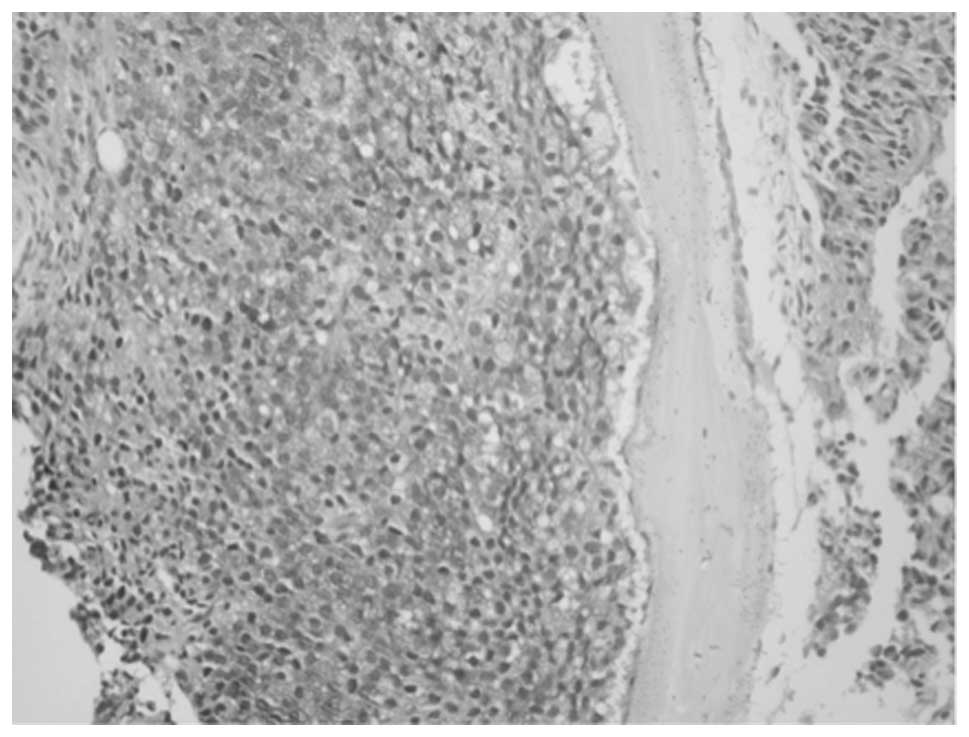

CT staining in benign acinii was predominantly localized to basal epithelium and was absent in secretory epithelium (Fig. 1). CTR expression displayed a similar profile (data not shown). Comparatively, CT/CTR immunostaining was absent/or weak in benign regions of the prostate, but was stronger in HGPIN and malignant acinii (Fig. 2A and B). Higher magnification images of a PC specimen suggest that basal epithelial cells displaying prominent nucleoli were strongly CT- or CTR-positive (Fig. 2C and D). Bone metastasis of PC displayed intense cytoplasmic CT staining, suggesting tumor cells may secrete CT after implanting in the bone (Fig. 3).

Prostate specimens from pathology as well as TMA showed considerable variability in CT/CTR staining (Fig. 5). Specifically, benign specimens showed very weak stainings that increased to very strong in metastatic PCs.